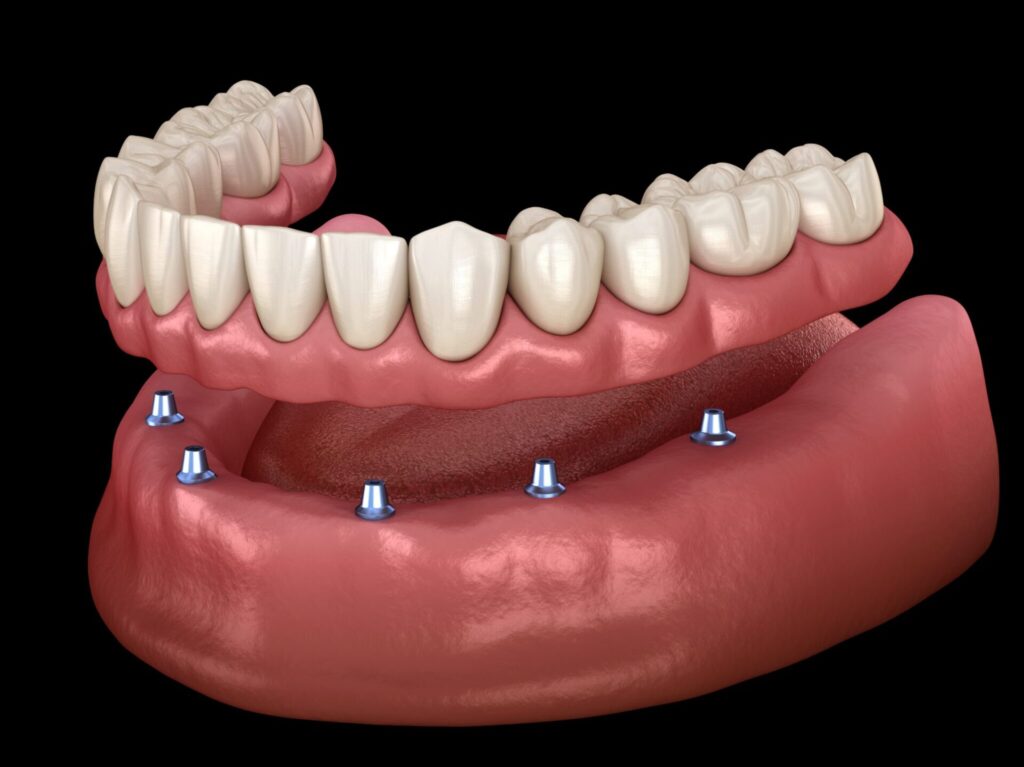

②インプラントオーバーデンチャー(総入れ歯の方で、負担を抑えたい方へ)

顎の骨に2~4本のインプラントを埋め込み、それを「土台」として総入れ歯をしっかりと固定する方法です。

【メリット】

総インプラント治療よりも手術の負担や費用を抑えられます。入れ歯がインプラントでしっかり固定されるため、動かず・外れにくくなり、会話や食事が格段に楽になります。